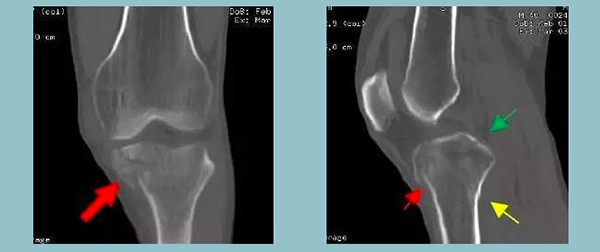

我们看到在第一张正位图像上,已然可以确诊王伯伯左侧腓骨上端撕脱骨折了。

在第二张侧位图像上,箭头指向处,我们可以看见胫骨外侧平台有异于正常结构的透亮线影(我们可以把它想作吐司上的小黑点)此处应高度怀疑骨折!为了不漏诊,我们再加做CT检查。

真是一做吓一跳!不仅对于平片上圆圈内已确诊的腓骨上端撕脱骨折,在CT影像中也能清晰看见,对于刚刚深深隐藏在平片中的“小病魔”——可疑透亮线影,被暴露无遗地展现在CT影像中。

通过二维重建图像,我们确诊患者为胫骨平台多发骨折(不同颜色箭头指向各个骨折部位)。看完CT报告之后,我们可以确诊:王伯伯左侧腓骨上端撕脱骨折、胫骨平台多发骨折。